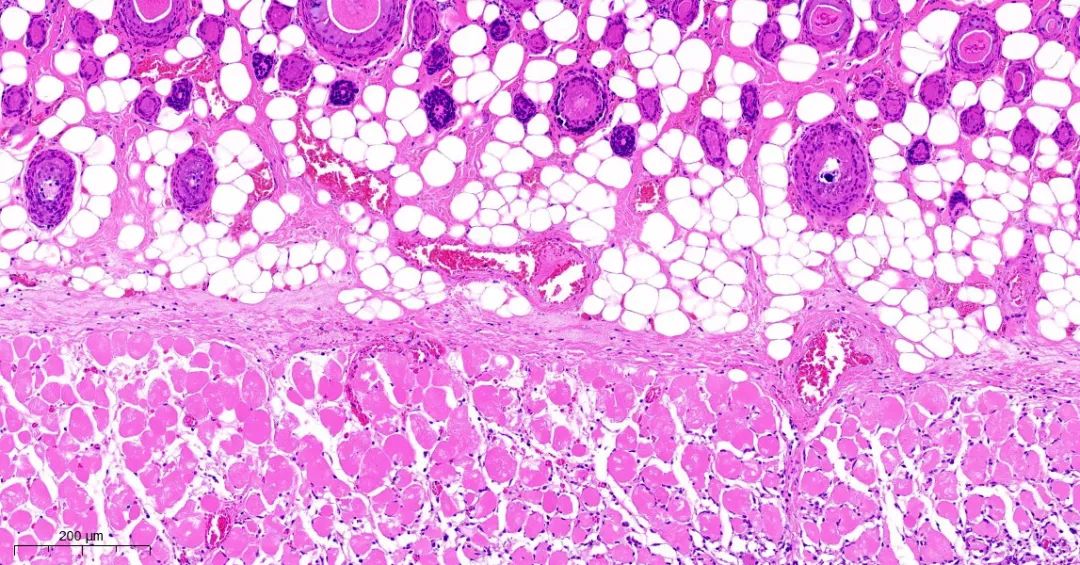

取正常对照组及模型组大鼠背部皮肤标本,常规固定,石蜡切片,HE染色,观察皮肤组织学变化。

模型1组皮组织切片对比

模型2组皮组织切片对比